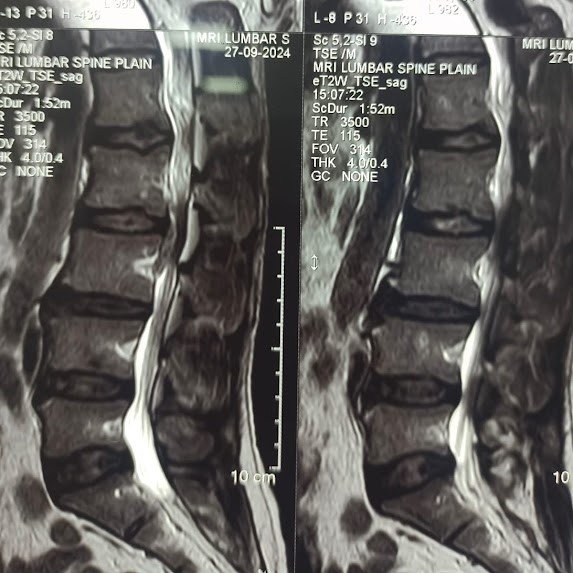

Condition:

Cauda equina syndrome is a serious condition where severe compression of the nerve roots occurs in the spinal canal.

Symptoms:

Leg weakness, numbness, loss of bladder or bowel control, and severe lower back pain. It is a medical emergency.